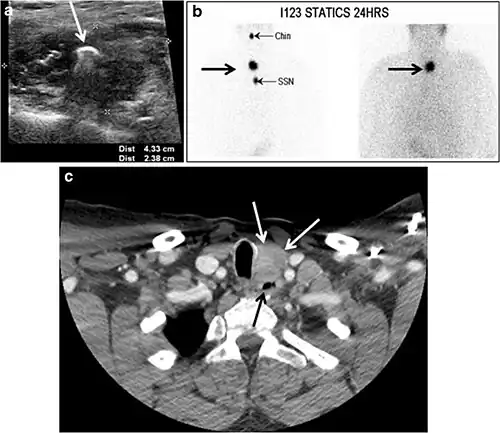

Fig. 7. A 51-year-old female patient post total thyroidectomy for PTC with elevated thyroglobulin measurement. an Axial non-enhanced CT scan of the neck at the level of the thyroid bed demonstrates a well-defined, rounded, homogenously dense soft tissue situated between the trachea and left internal jugular vein (white arrow). b Transverse ultrasound image of the neck demonstrates a well-defined, homogeneous, hypoechoic soft tissue nodule measuring 6 mm (white arrow) with no detected micro-calcifications. Biopsy showed a predominantly residual normal thyroid tissue with micro-foci of PTC.[1] -

Fig. 18. Lingular thyroid in a 33-year-old male who presented with oropharyngeal bleeding. an Axial enhanced neck CT scan at the level of mandible demonstrates a 3 × 3 × 3.4 cm round, partly well-delineated, heterogeneously enhancing lesion (white arrow). It is predominantly on the left side of the oropharynx and to some extent at the mid part of the base of the tongue. The thyroid gland was normal (not shown). b Image of the anterior face and neck taken 20 minutes after Tc99m-Pertechnetate injection shows absent thyroid radiotracer uptake in normal thyroid anatomical location (black short arrows). There is an area of increased uptake (long black arrows) corresponding to the posterior tongue mass identified on CT scan.[1]